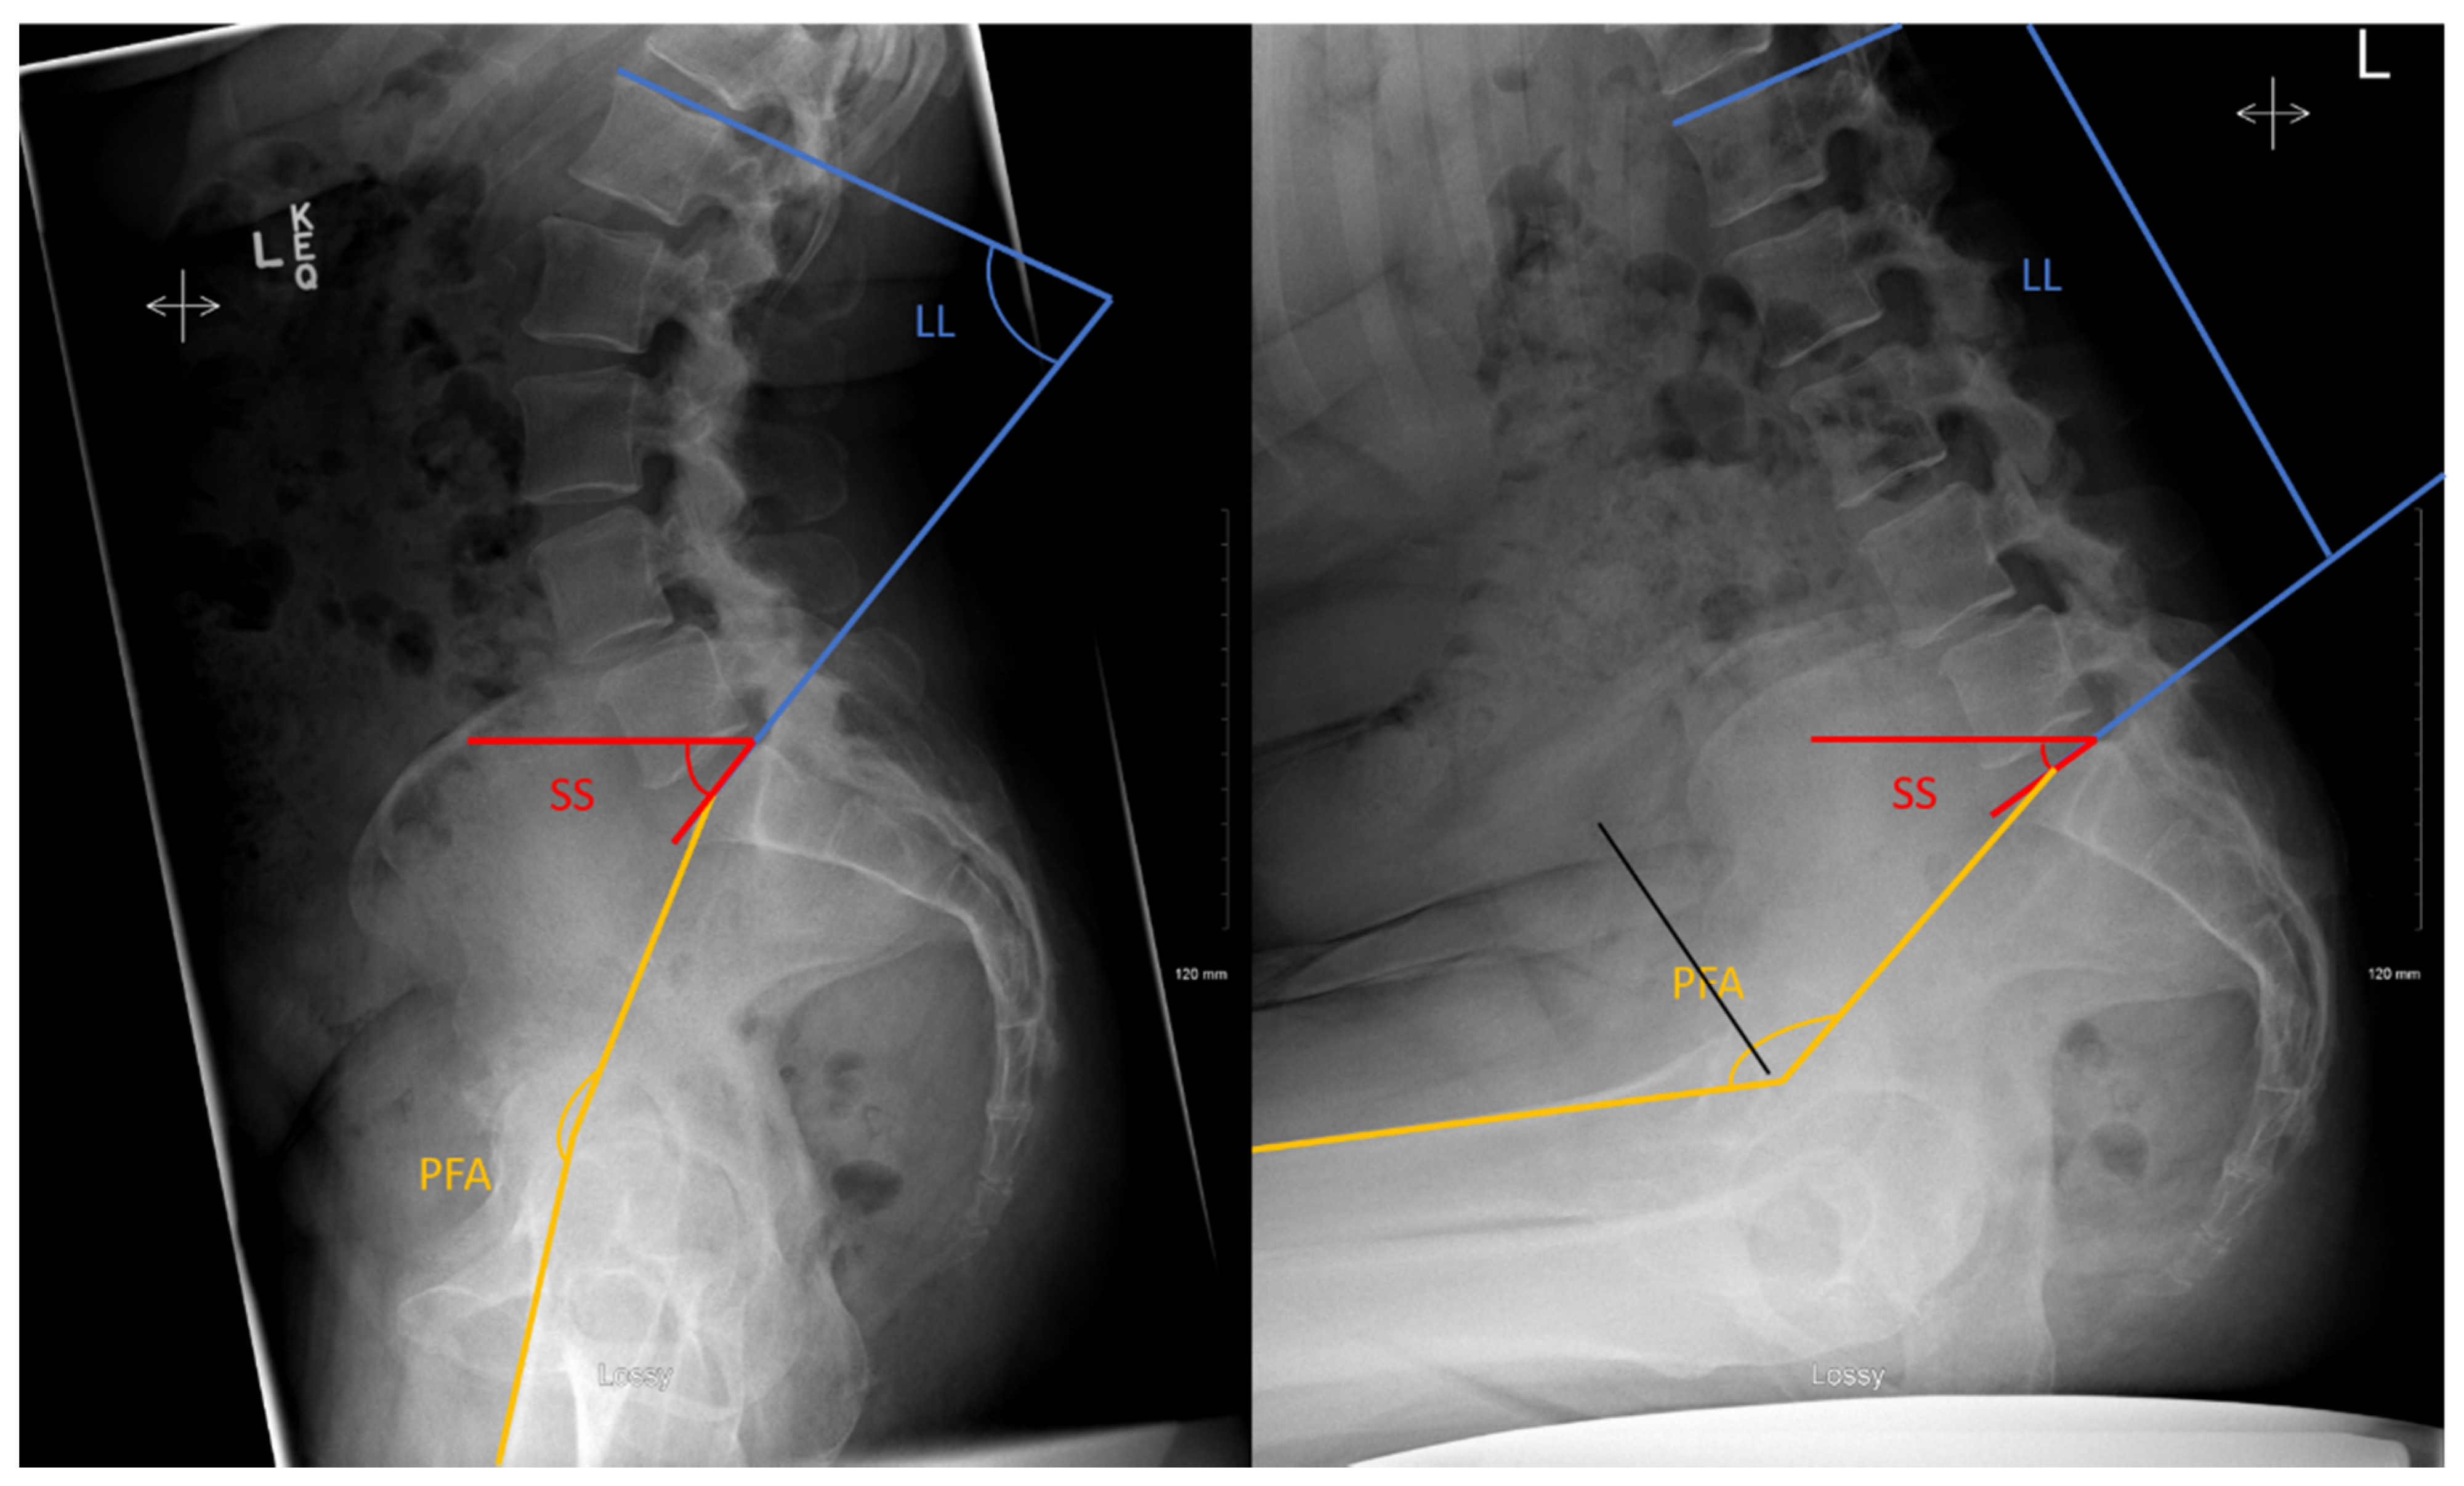

All participants underwent two lateral spinopelvic radiographs of pelvis, hip, and proximal femur in (1) standing spine; and (2) seated deep flexed forward. This was chosen because it is considered a position of increased dislocation risk and has been shown to better characterize the spinopelvic characteristics of THA patients and assess maximum lumbar flexion [18,19]. Radiographic measurements of the sacral slope (SS), pelvic–femoral angle (PFA) and lumbar lordosis (LL) angles were performed in both positions, as defined in Figure 1. All assessments were measured by a single observer twice. The changes in SS equal the changes in pelvic tilt (PT).

Figure 1.

Lateral view of the lumbar spine and pelvis from the standing (left) and seated deep flexed forward (right). With angles calculated for sacral slope (SS), which is the angle tangent to the S1 endplate and a transverse line; pelvic femoral angle (PFA) defined as an angle based on a line from the center of the S1 endplate to the center of the femoral head and a second line that parallels the diaphysis of the femur; lumbar lordosis (LL) being a line tangent to the S1 endplate relative to a line tangent to the superior L1 endplate. The changes in SS were considered equivalent to the changes in pelvic tilt (PT).